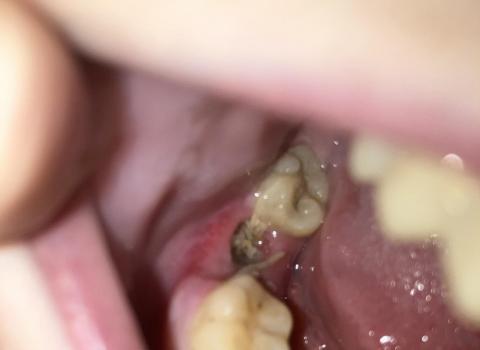

Case Analysis: Cervical Caries (Zoom 100%)

In this dental case, decay is visible near the cervical area — the region where the crown of the tooth meets the gum line — rather than on the chewing surface or fissures. Cervical caries are often overlooked, but they can progress silently and cause significant tooth sensitivity or even nerve damage if untreated.